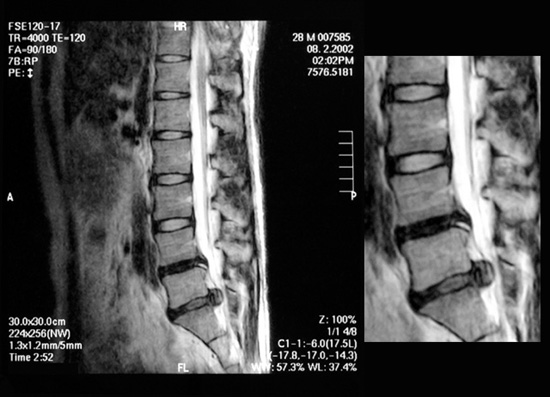

掲載したMRI画像は典型的な腰椎椎間板ヘルニアで、髄核が後方に脱出し、脊髄や神経根を圧迫している様子が容易に見て取れます。腰椎椎間板の繊維輪(外側)の硬さは硬いゴム程度ですが、ひび割れた繊維輪から脱出した髄核(内側)の硬さは硬めのジャム程度、『体外から押し込む』…奇跡です。